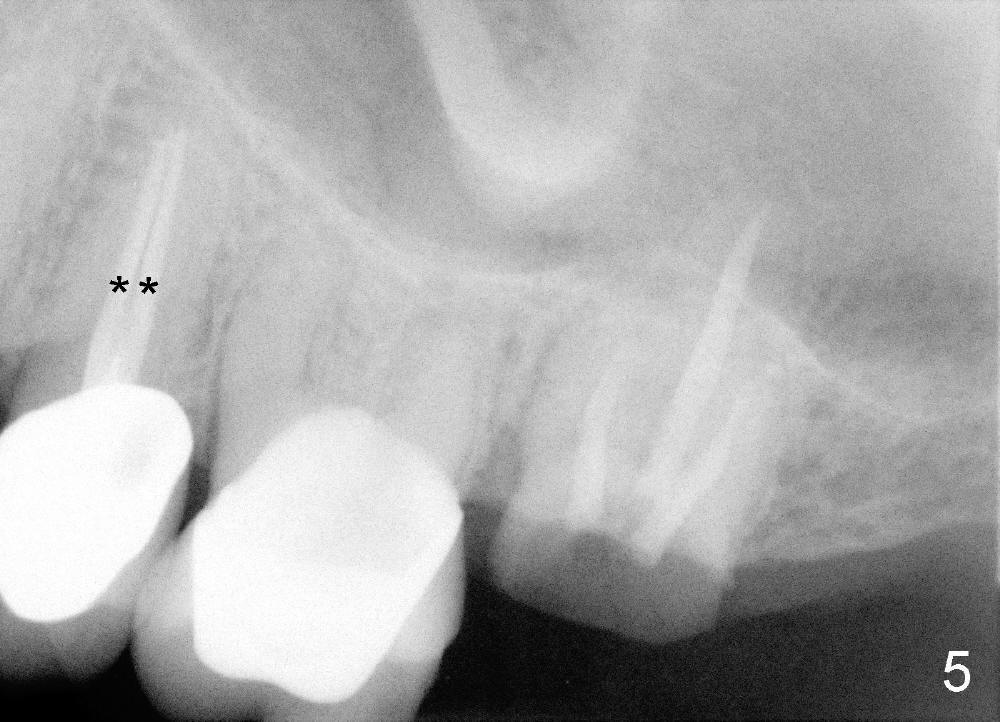

陈先生五十来岁,牙齿不好,右上有一个三个单位桥(图一:5-7),右下四个单位桥(5-8)。五年前他第一次来诊所时左上7有牙髓炎症状(图二),那颗牙齿有很大银汞充填物(A),之下出现龋齿(*)。出于救死护伤精神,开始做根管治疗(图三:*牙胶尖),当时他原来牙医出差了,之后给左上7戴上牙冠(图四:C)。其实图四X光片拍摄是在左上7根管治疗之后一年半,这次左上5有牙髓炎症状,再次为他做根管治疗(图五:*)。他又很久才回来:两年半,这次问题更严重:左上7断了(图五),好在他毫无怨言,可能与他是修理工有关,牙齿也需要修修补补。他也知道现在必须做植牙,这时我们非常自豪告诉他我们能做植牙,他便回家凑钱。一年半后他又从天降,左上问题还没有解决,右下8基牙在桥下出现龋齿(图六:^),必须拔除,这时右下6,7必须先做植牙(图六:植牙设计;N:下齿槽神经; L:颏神经襻(loop))。末端缺牙做活动义齿效果不好,据研究表明它只能恢复百分之十咀嚼功能,而植牙百分之百。